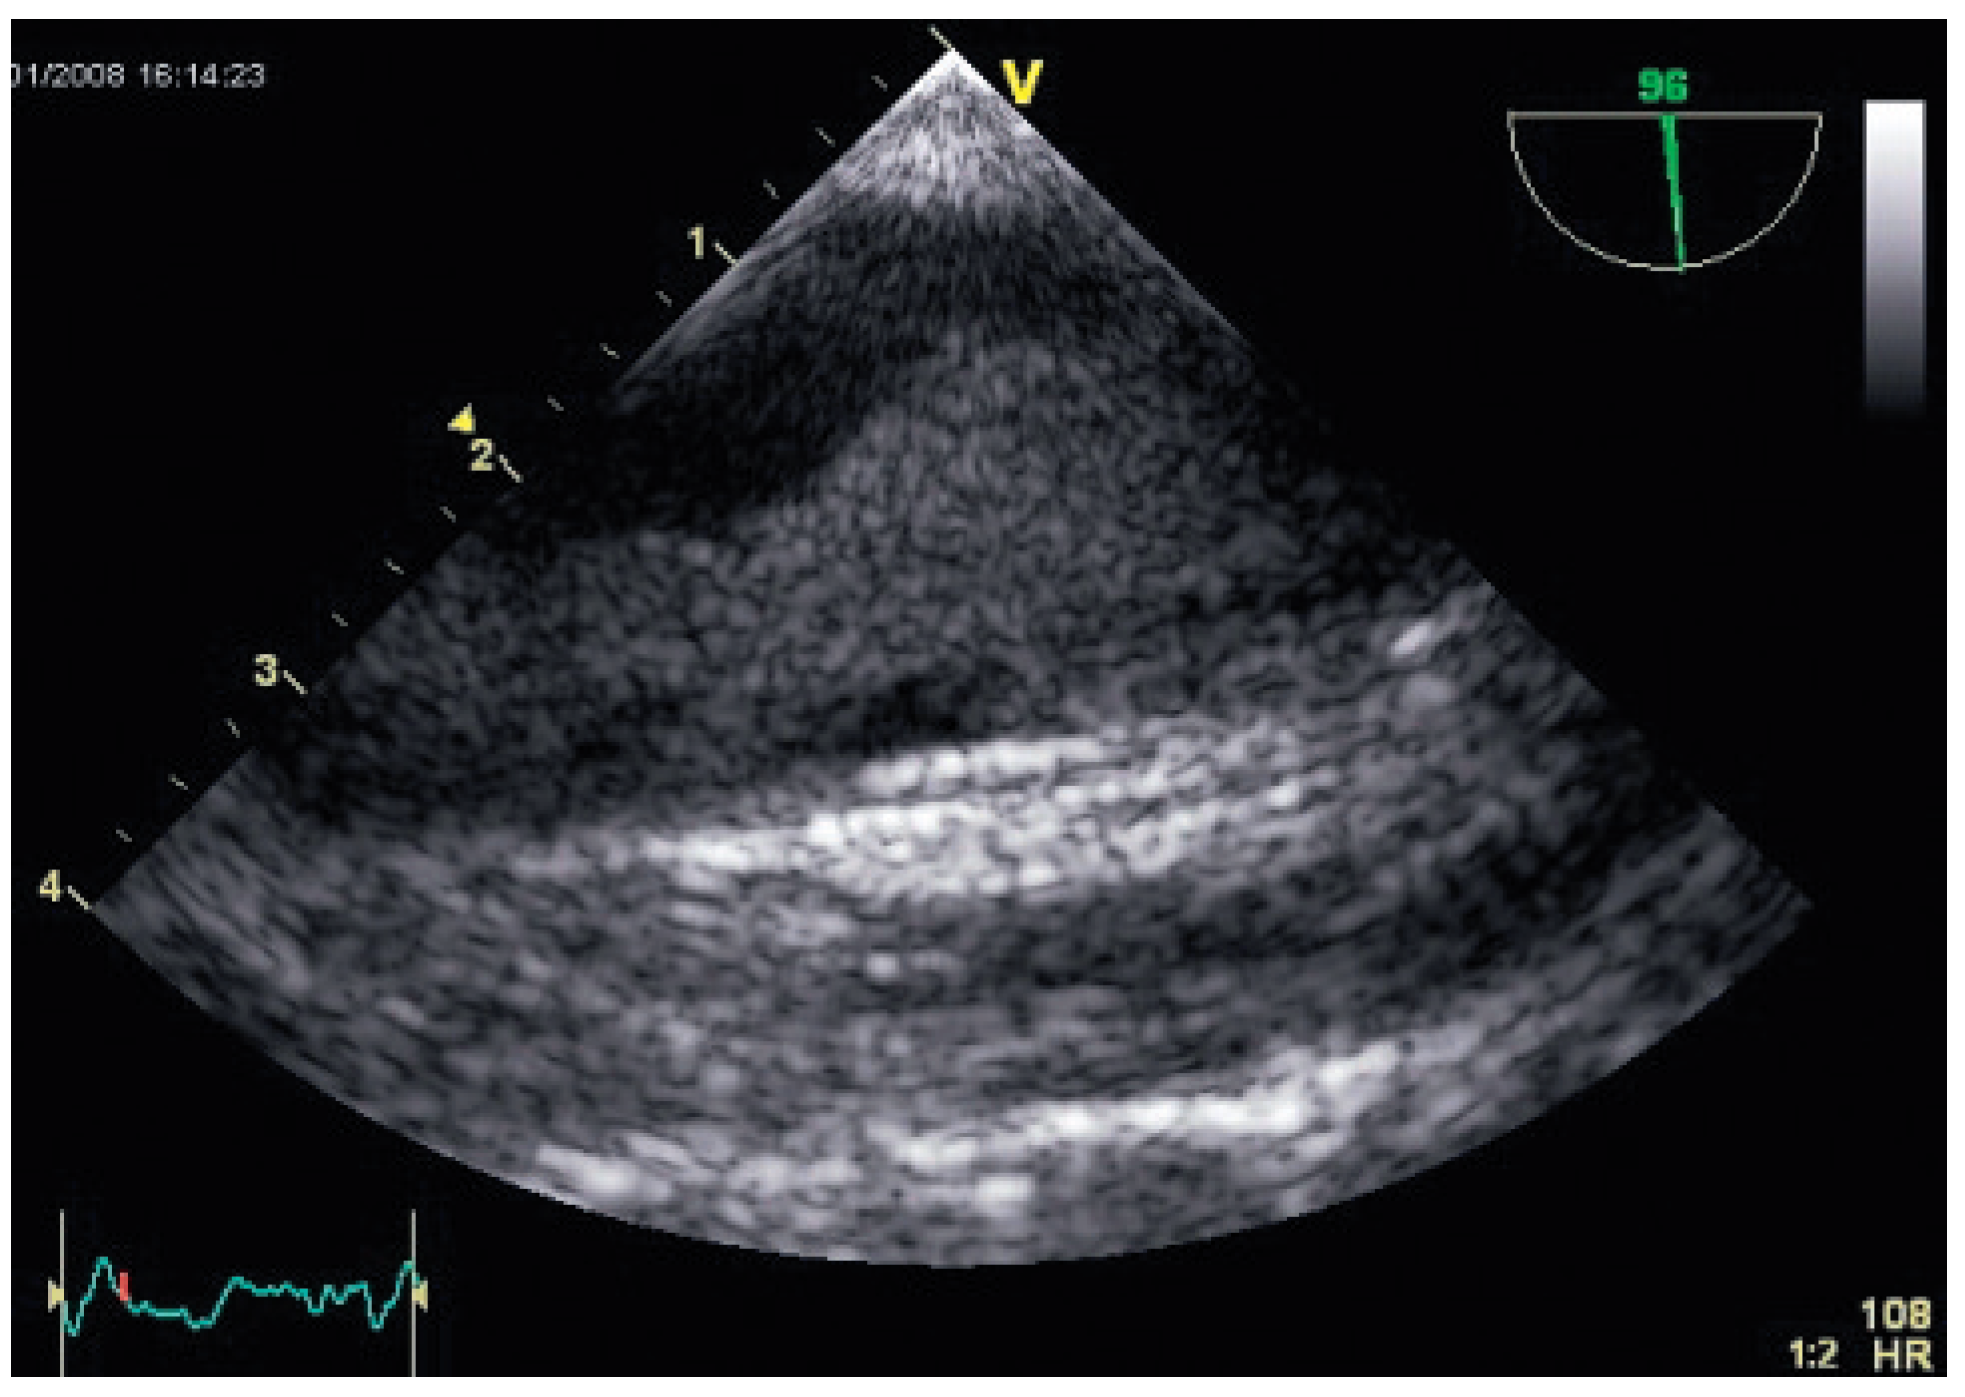

Flottierender Thrombus in der Aorta Descendens